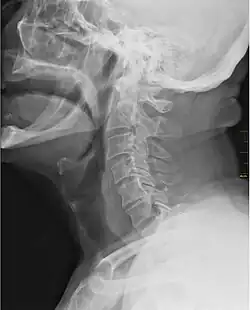

Го́рло[1][2][3] — часть шеи впереди позвоночного столба.

Верхней границей является подъязычная кость, нижней — рукоятка грудины и ключица. Термин «горло» является общеупотребительным, но не анатомическим. Он отсутствует в списке новейшей анатомической терминологии 1997 года[4]. Устаревшее слово означавшее горло — Жерло[5]. Через горло проходят многочисленные жизненно важные органы и системы: